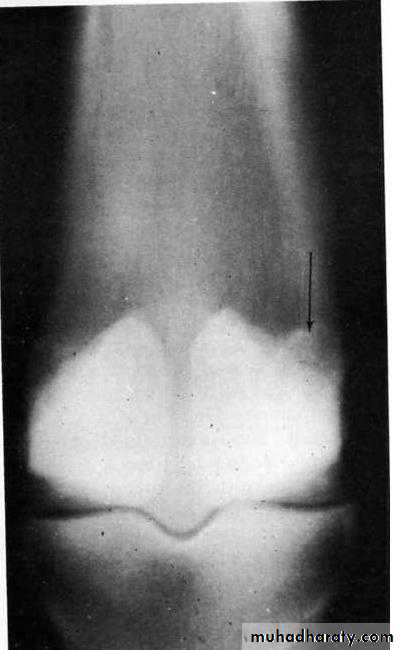

On radiographic examination a subperiosteal callus is usually observed.

A broad base subperiosteal callus on the dorsal medial surface of the third metacarpal bone (arrow) typical type 2 dorsal metacarpal disease.